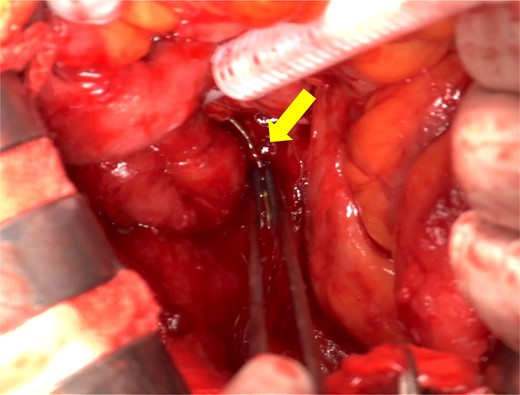

A male in his 40s was diagnosed with vEDS 5 years ago and has been followed up at our internal medicine department. His medical history included spontaneous mesenteric artery rupture and sigmoid colon perforation, for which he underwent two laparotomies. He presented to our hospital with a chief complaint of right lower abdominal pain. Physical examination revealed tenderness in the right lower abdomen without signs of peritoneal irritation. Laboratory tests showed slightly elevated inflammatory markers as follows: white blood cell count: 8000/μl, C-reactive protein: 6.51 mg/dl. Contrast-enhanced computed tomography revealed a foreign body in the ileum with bowel perforation (Fig. 1). Free air was localized in the mesentery and no abscess formation was observed. A detailed inquiry into the onset of abdominal pain revealed that he had consumed codfish 6 days prior. Based on these findings, the patient was diagnosed with a small bowel perforation caused by a fish bone. Although surgery for a patient with vEDS involves the risk of fatal complications, emergency laparotomy was performed due to the potential for injury to other organs or blood vessels and the risk of peritonitis from the migration of the fish bone. Intraoperative findings showed severe adhesions of the small intestine and a sharp 4 cm foreign body (fish bone) located 15 cm proximal to the terminal ileum penetrating the mesentery through the ileal wall (Fig. 2). We removed the foreign body and confirmed that it is a fish bone (Fig. 3). We resected ~5 cm of the small intestine, including the perforation site, and performed a stapled anastomosis. The patient developed postoperative paralytic ileus, which improved with conservative treatment using a nasogastric tube, and he was discharged on postoperative Day 27.

Intraoperative findings. Severe adhesions of the small intestine were observed and a sharp 4 cm foreign body was located 15 cm proximal to the terminal ileum penetrating the mesentery through the ileal wall (arrow).